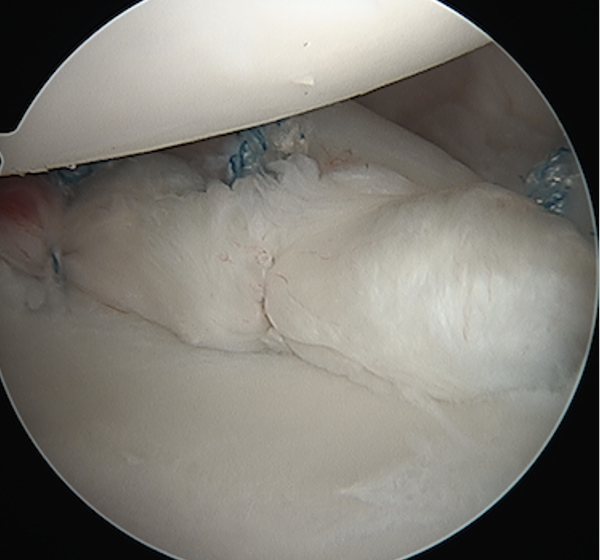

Arthroscopy

Capsule tear anteriorly, extending up into humeral insertion

Side to side suture repair +/- HAGL repair

Side to side repair of capsular tear

Intact anterior labrum with capsular tear, axillary nerve seen below capsular tear in axillary recess